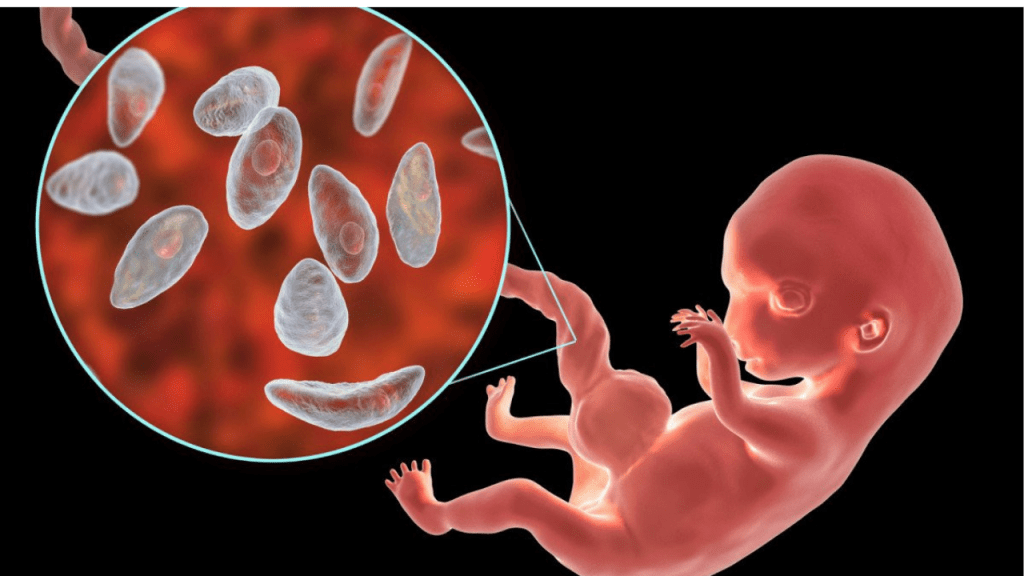

Toxoplasma gondii es un parásito microscópico que infecta aproximadamente a un tercio de la población mundial. Su huésped definitivo son los gatos, donde se reproducen, pero los humanos pueden infectarse al entrar en contacto con heces contaminadas o al consumir carne poco cocida.

En la mayoría de las personas sanas, la infección no produce síntomas evidentes. Tras la fase inicial, el parásito forma quistes tisulares en órganos como el cerebro, los músculos y el corazón. Durante años, estos quistes se consideraron estructuras completamente inactivas.

La investigación liderada por Emma H. Wilson y su equipo utilizó secuenciación de ARN unicelular en modelos animales para analizar el contenido interno de los quistes de Toxoplasma gondii. El resultado fue inesperado: dentro de un solo quiste coexisten múltiples formas del parásito.

Algunos subtipos mostraron señales de actividad metabólica, mientras que otros parecían estar más cerca de reactivarse. Esto indica que el quiste no es un refugio pasivo, sino un centro dinámico donde el parásito toma decisiones clave sobre su desarrollo.

La toxoplasmosis suele ser leve, pero puede causar complicaciones graves en personas con sistemas inmunológicos debilitados, como pacientes trasplantados o con VIH. También representa un riesgo durante el embarazo, debido a posibles daños al feto.